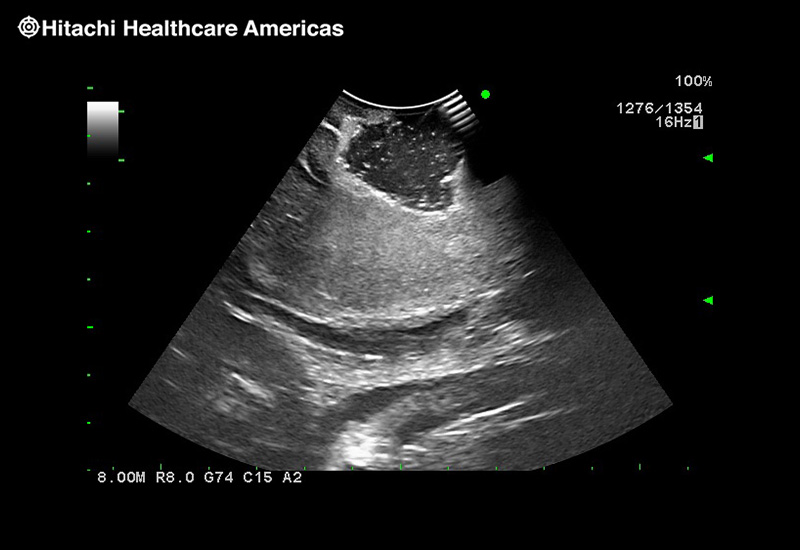

Superior guidance for all applications

Fujifilm Healthcare Americas is committed to designing tools that help surgeons navigate inside the human body and provide the necessary information to immediately make critical surgical decisions.

Fujifilm Healthcare's dedication to Surgeons provides outstanding ultrasound technology, professional support and the specialized tools necessary to best perform comprehensive real-time ultrasound imaging in Breast Surgery, General Surgery, Laparoscopic Surgery, Neurosurgery, Robotic Surgery and Surgical Oncology.

Recognized for our outstanding image quality, outstanding system reliability and intuitive use of cutting edge technology, Fujifilm Healthcare remains the standard in the field of Surgery.

Recognized for our outstanding image quality, outstanding system reliability and intuitive use of cutting edge technology, Fujifilm Healthcare remains the standard in the field of Surgery.